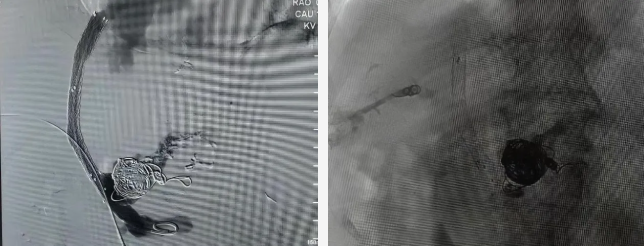

手术在局麻下顺利开展。术中DSA造影证实门静脉主干不显影,团队凭借精湛技术,严格按照术前方案,精准穿刺门静脉分支,成功建立肝静脉与门静脉之间的人工分流通道,并顺利植入支架以维持血流畅通,同时对出血血管进行栓塞处理。

△术中

术后患者门静脉压力下降45%,出血得到有效控制,腹水逐步吸收好转。

△术后